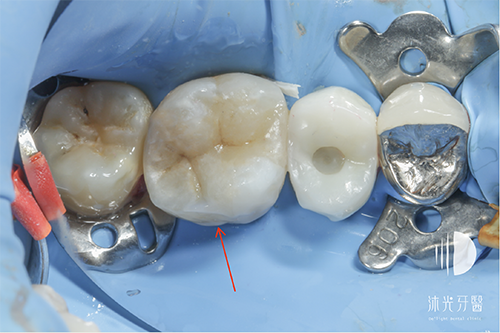

陶瓷嵌體黏著到位